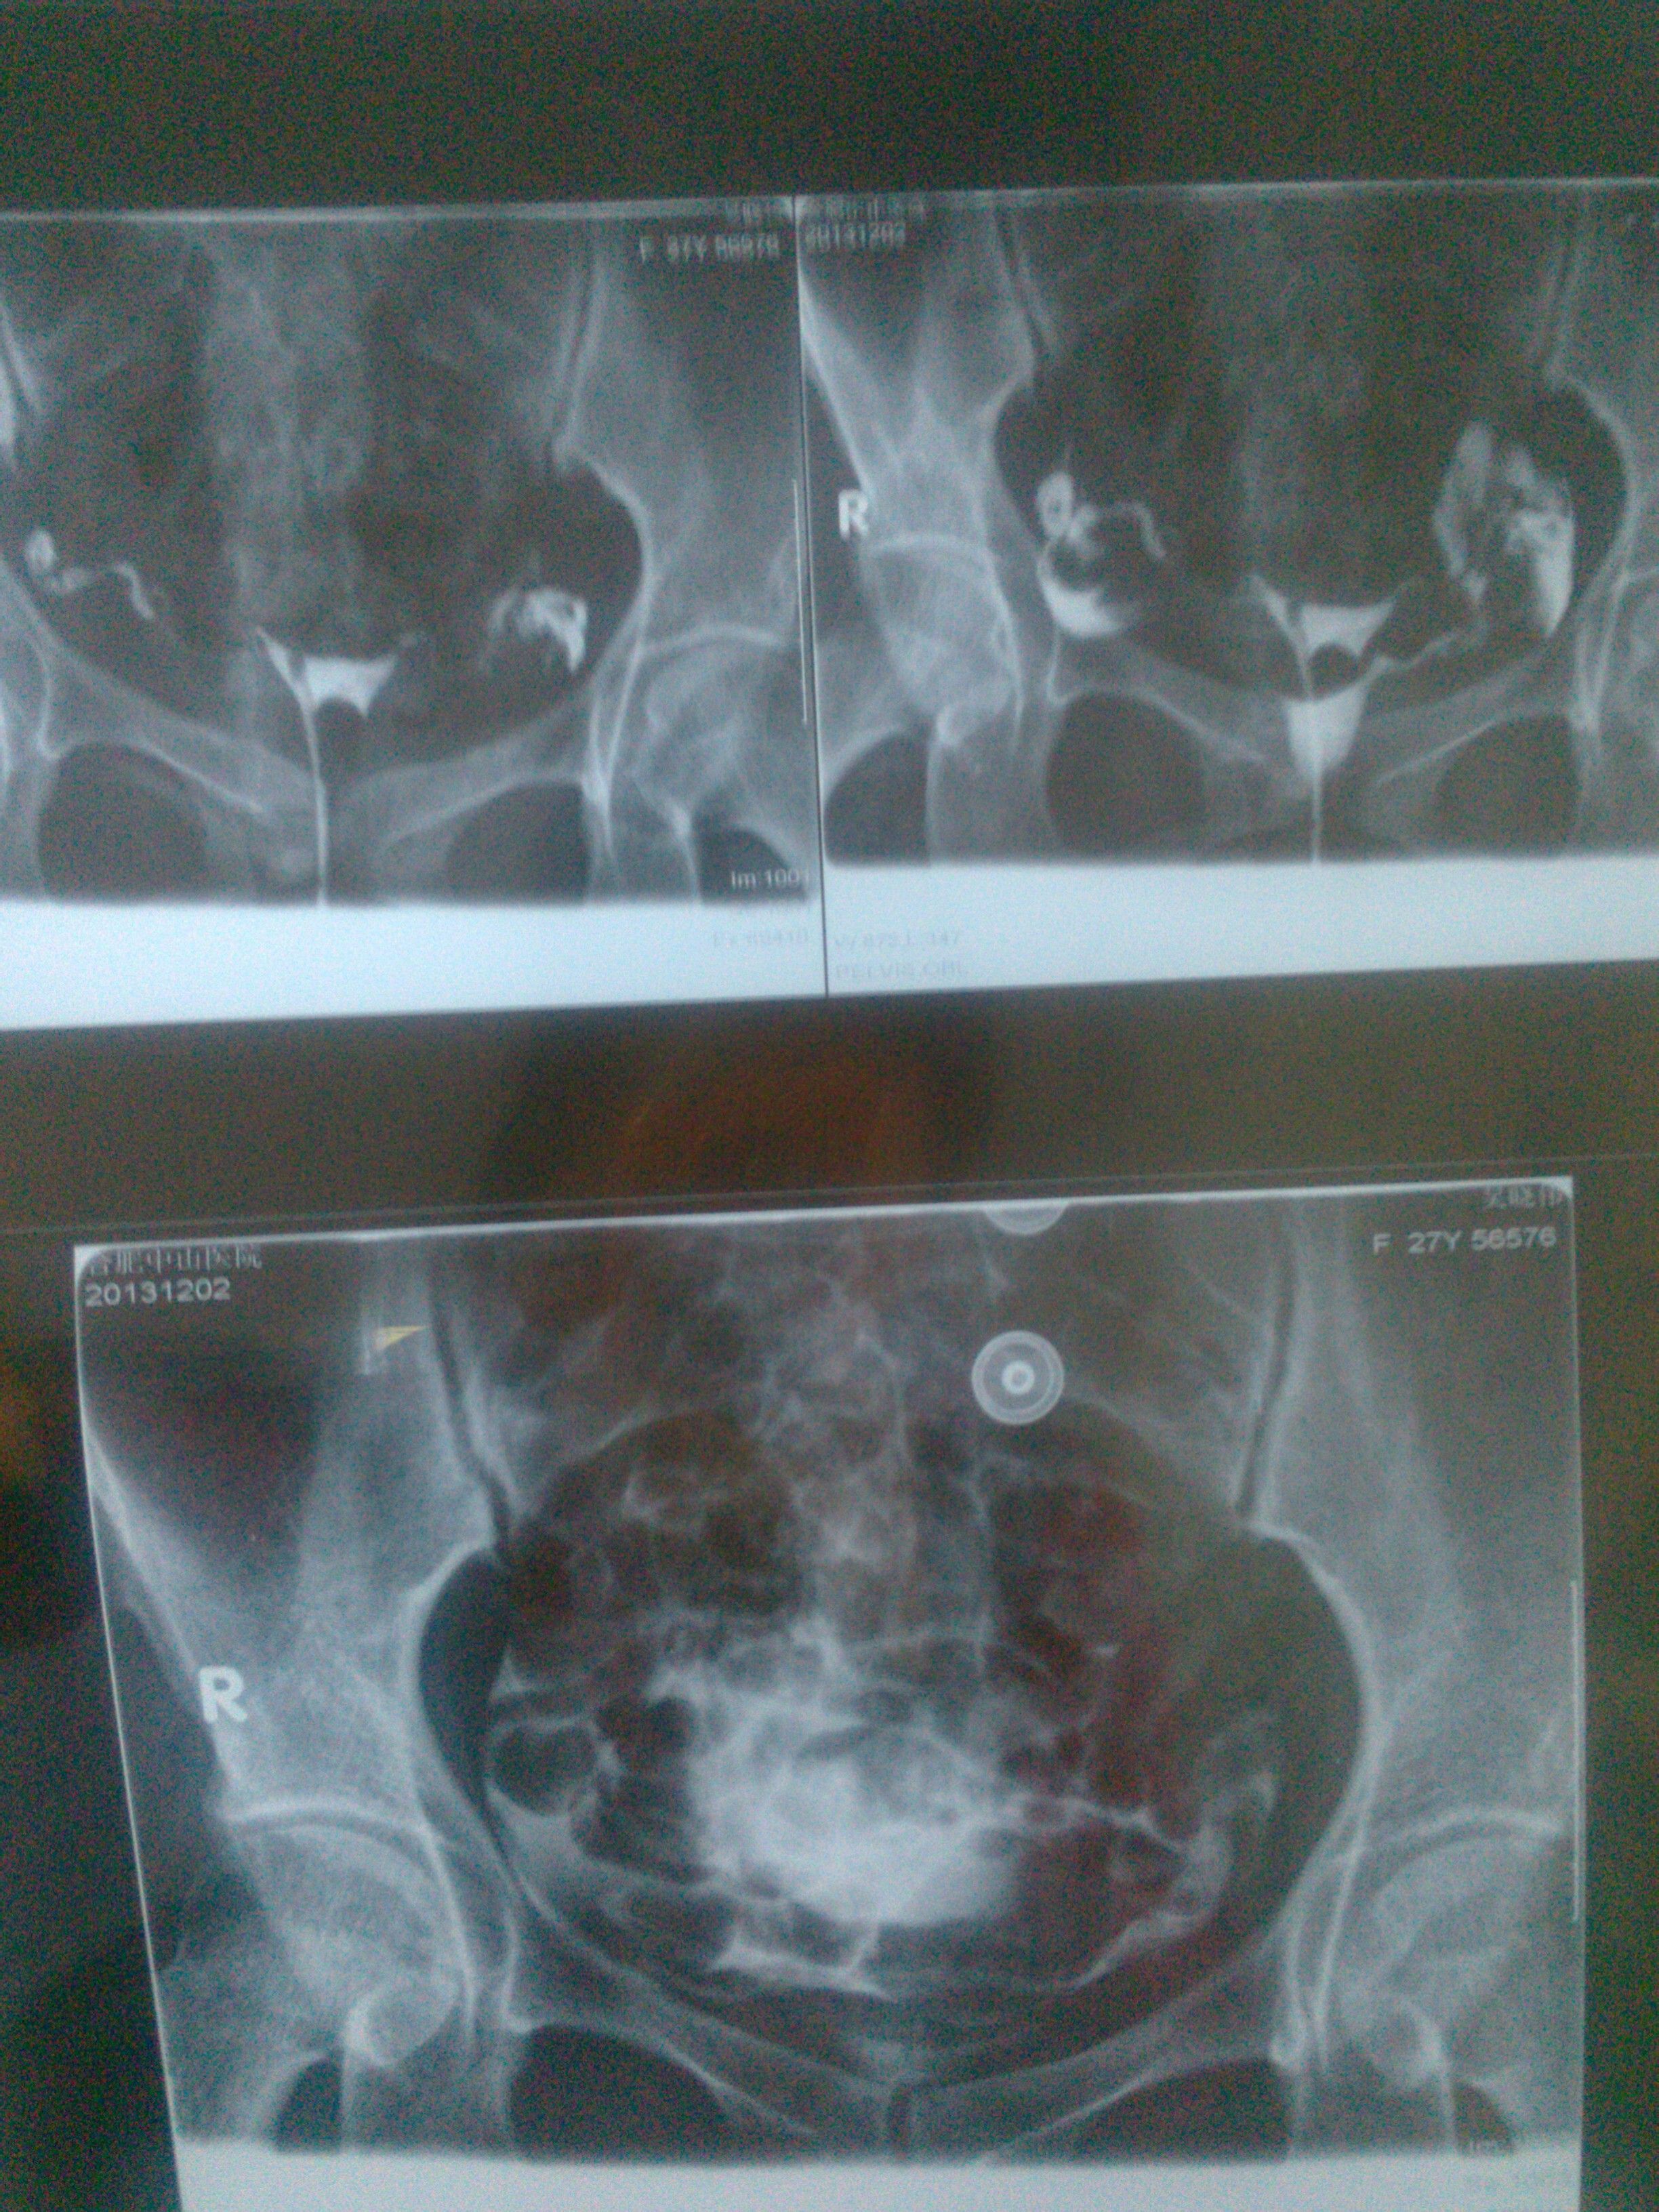

医生你好 这是我做的输卵管造影,结果是通而不畅 医生也说有盆腔粘连(可能)不确定 我心里没底 我 还要做哪些检查 进一步知道自己真的盆腔有炎症呢?还有帮我看下 这片子很严重吗?影响怀孕吗? 点击展开 匿名用户 2013-12-04 17:08 为您推荐: 其他回答 病情分析: 你好;盆腔炎一般症状为下腹部有下坠感腰疼分泌物多有异味, 指导意见: 可以服用妇科千金片可以到医院做理疗再严重要打消炎针要注意卫生. 赫亦凝_2Vv0 2013-12-04 17:24 相关问题 我做造影检查出,输卵管炎和盆腔粘连,以前有怀过一个,做了人流,医生要我做个腹腔镜,不知道怎么办? 你好,我想问一下,我做完输卵管造影两个月后来月经时下面就有像鼻涕一样的粘糊糊长条是怎么回事啊? 你好大夫!我是这个月9号做的输卵管造影,中间也有几次肚子疼本来是这个月28号来月经,可是今天就来了